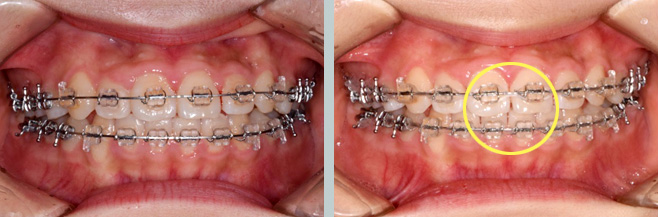

앞니가 고르지 못하면서 측절치가 뒤에서 나와 거꾸로 물립니다.

앞니가 안으로 기울어져 치아 각이 작아 이로 인해

아랫입술이 얇고 함몰되어 보입니다.

안으로 기울어진 앞니의 각도 개선 및 뒤로 빠져있는 측절치의

배열공간 확보를 위해 오픈코일스프링을 적용합니다.

거꾸로 물리는 측절치를 앞으로 당기는 견인을 진행합니다.

이때 측절치가 넘어오는 과정에서 주변 치아의 교합력에 방해받지 않도록 바이트블록(biteblock)도 부착합니다.

측절치가 앞으로 넘어오면 교정장치를 부착해 다른 치아들과 함께

배열합니다. 교정 중 앞니가 뻐드러지는 경향을 보이면 치간 삭제 후

앞니 각도를 조절합니다.